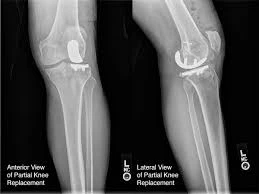

Orthopedic surgery

Surgery that involves your joints requires physiotherapy afterwards to regain full-body mobility. Knee and hip replacement operations are some of the most common procedures. Your orthopedic surgeon has specific recommendations for you after you have had your surgery. Orthopedic physiotherapists can help you with your recovery process after surgery and ensure that you don’t re-injure yourself.